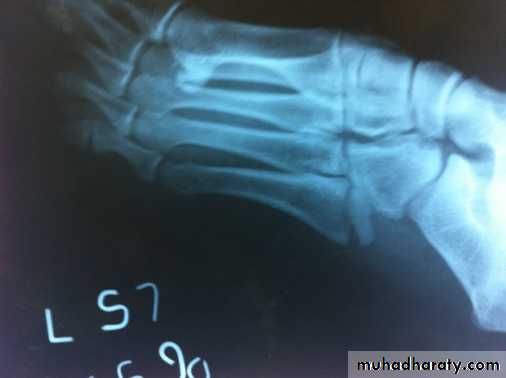

Fracture base of 5th metatarsal

This injury is very common, caused by foot torsion. It is nearly always caused by a twisting injury in which the foot is forced into inversion and equines (planter flexion), the styloid process at the base of the 5th metatarsal being pulled off by the tendon of the peroneus brevis muscle, which is inserted into it . There is pain and tenderness over lateral side of foot. It regarded as muscle injury. Treated by pressure bandage and analgesia, if pain sever a below-knee walking plaster for 3 weeks.